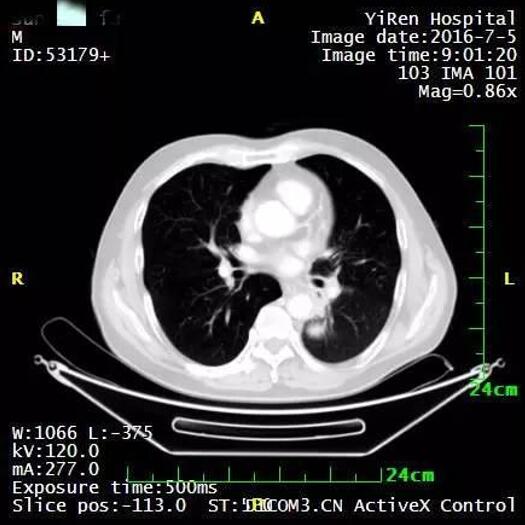

治疗后两个月进一步缩小

治疗后7个月,病灶几乎全部消退